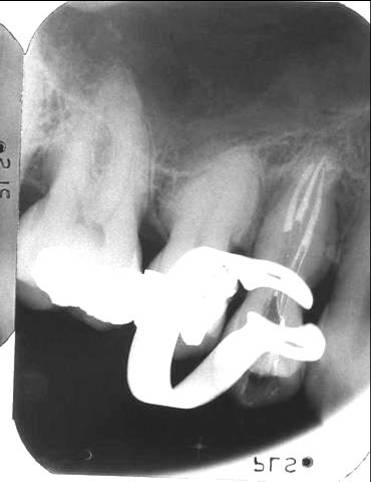

44, 45, 34 en 35

Vrijwel altijd is er sprake van ovale kanalen in bucco-linguale richting welke daarom moeilijk op een X-foto te zien zijn. Soms lijkt het kanaal op 4 a 6 mm vanaf de apex dicht te zitten. Ook op de X-foto is dan geen kanaal te zien. Hier is vaak sprake van een splitsing in meerdere kanalen. Als het coronaire deel goed gereinigd is, valt met de OPMI te zien of er een splitsing aanwezig is en in welke richting de kanalen lopen. Als tussentijds CA(OH)2 is ingesloten lichten de gesplitste kanaalingangen heel mooi op. Ook bij het vullen van dergelijke kanalen is een OPMI onontbeerlijk (zie X-foto).